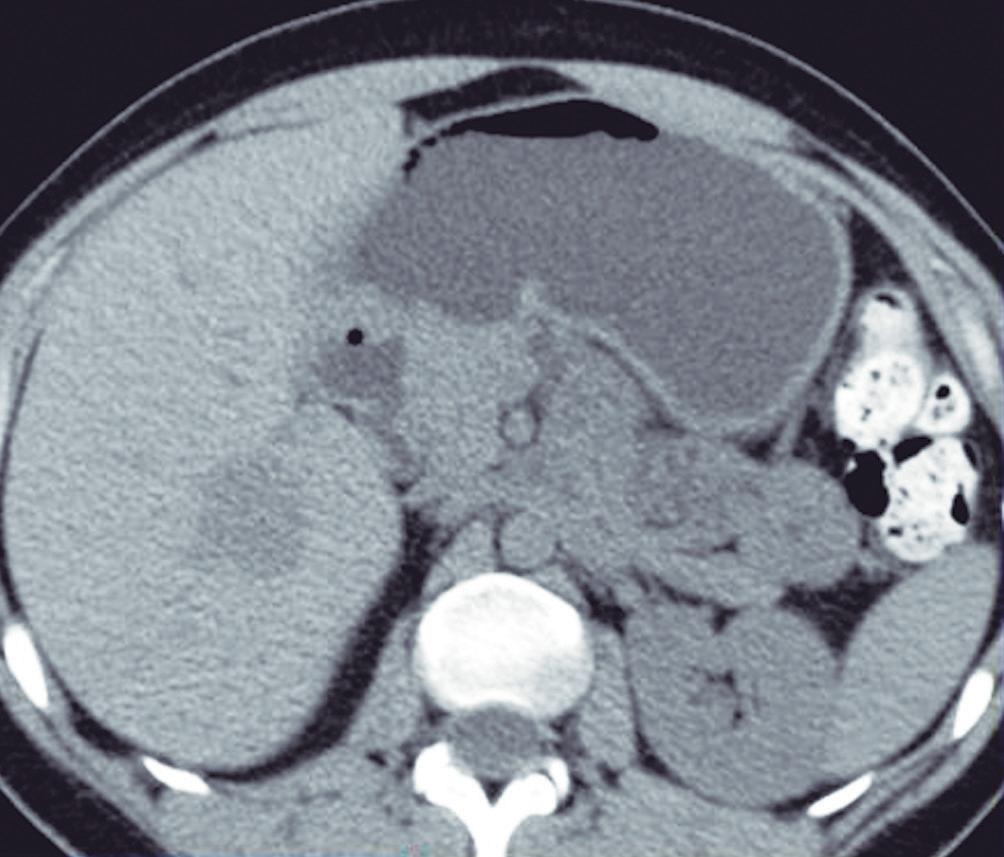

La esteatosis focal ocurre típicamente en el segmento IV del hígado, adyacente a la cisura del ligamento falciforme; carece de efecto de masa y no refuerza poscontraste. En ecografía suelen ser focos hiperecogénicos. En la TCMC son imágenes hipodensas de ubicación típica y en la RM, específicamente, demuestran caída de la señal en la secuencia T1 fuera de fase, lo que despeja cualquier duda diagnóstica. (Figura 8) En raras ocasiones, los depósitos de grasa pueden ser multifocales y plantear el diagnóstico diferencial con metástasis. En dichas situaciones el rol de la RM es clave para establecer un diagnóstico específico e inequívoco. Otra causa de sobrediagnóstico de lesión focal ocurre cuando el hígado presenta esteatosis difusa pero con zonas respetadas donde, tanto en la ecografía como en la TCMC, pueden generar confusión. En general, se aplican los mismos criterios ya que suelen ocurrir en sitios típicos como la región dorsal del segmento IV, carecen de efecto de masa, y la anatomía vascular se puede apreciar indemne en el seno de dicha área. En caso de duda diagnóstica, reiteramos que la RM es la técnica que permite dilucidar la naturaleza esteatósica del hallazgo.

B C